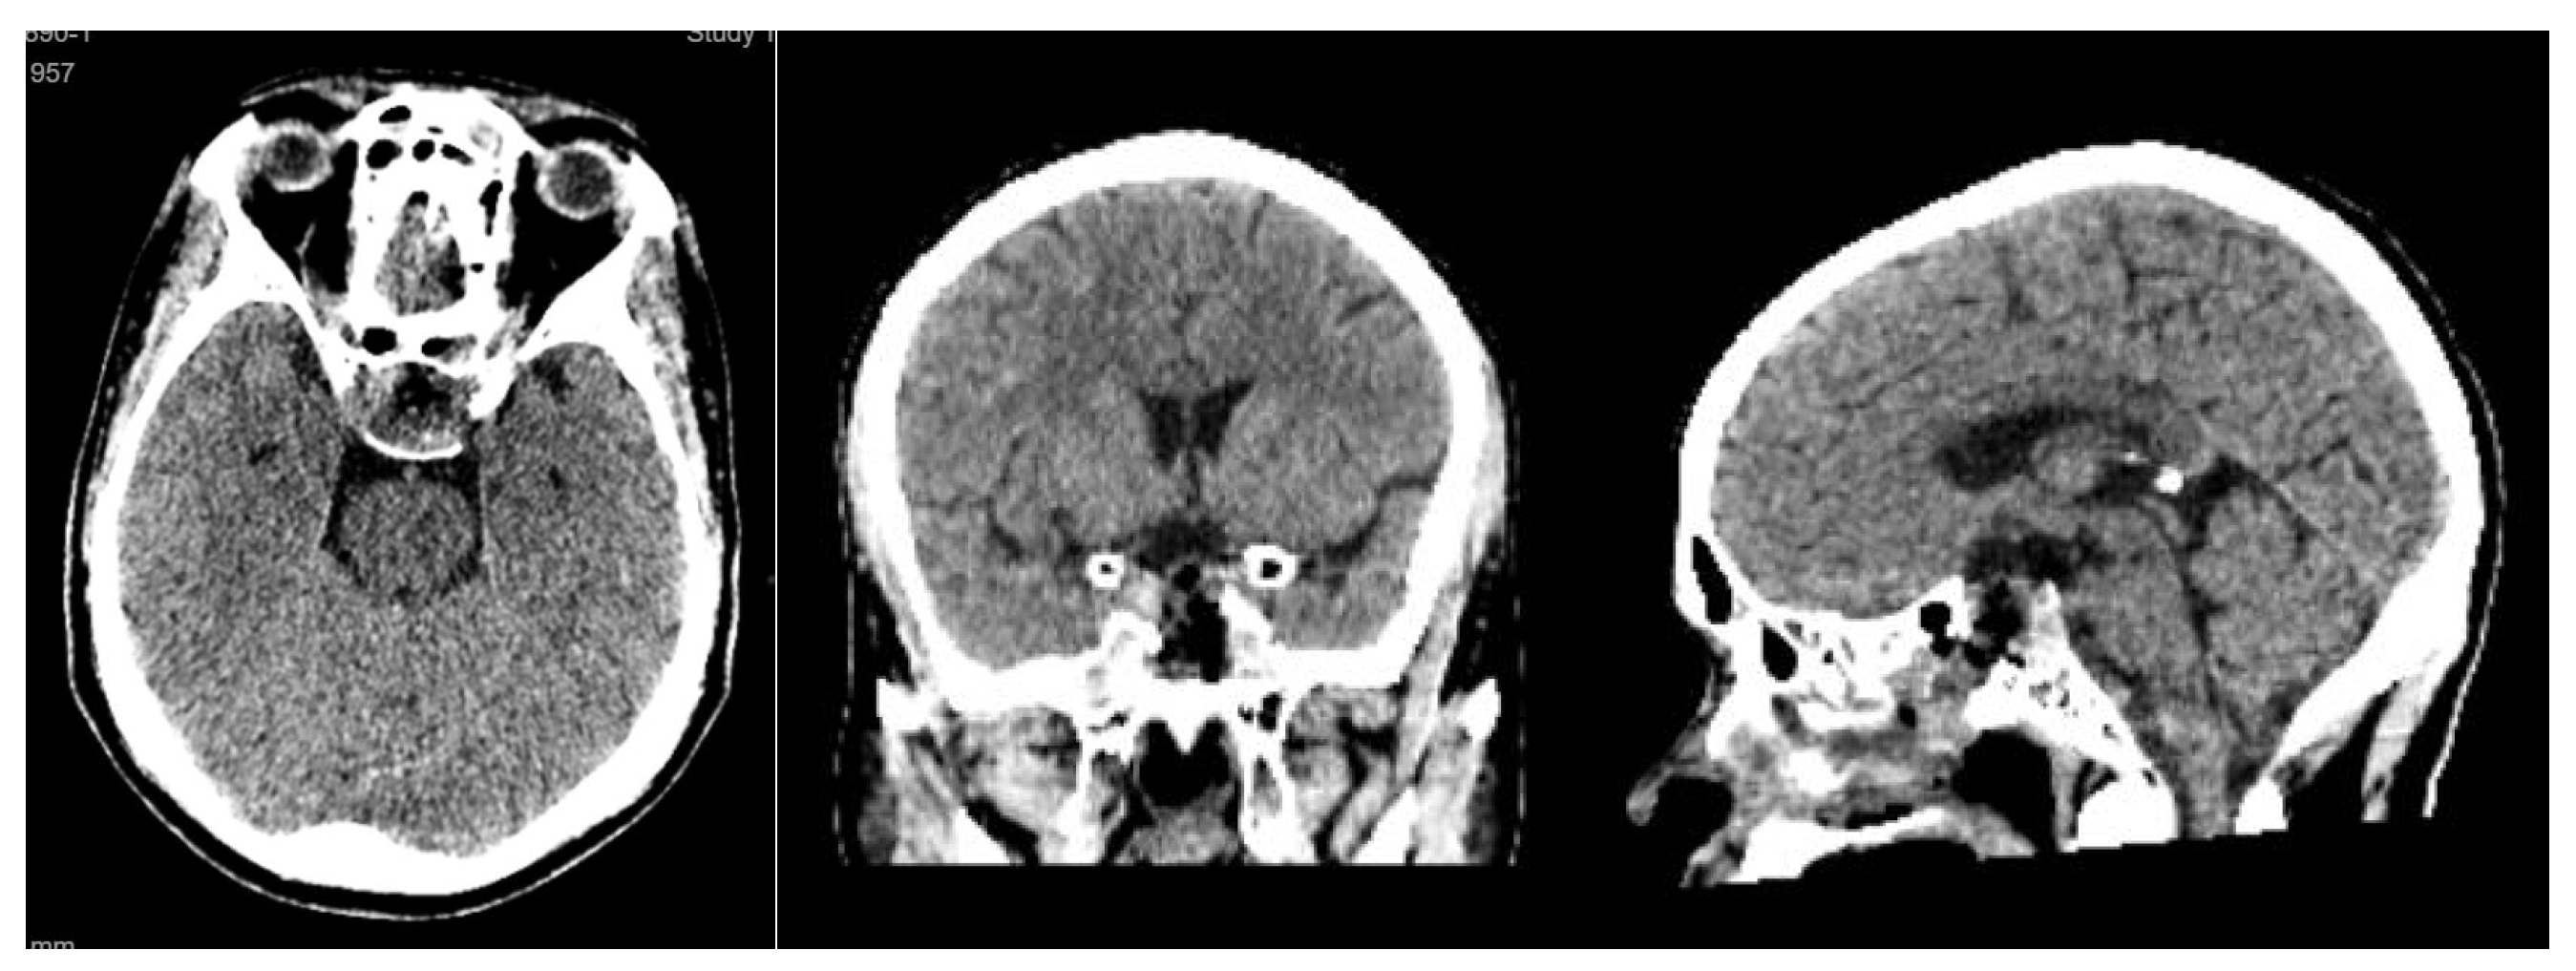

Postoperative imaging demonstrated near-total resection of the lesion with decompression of the optic apparatus and restoration of normal sellar anatomy (Figure 5).

Figure 5. axial, sagittal and coronal CT scan performed at day 1 after surgery.